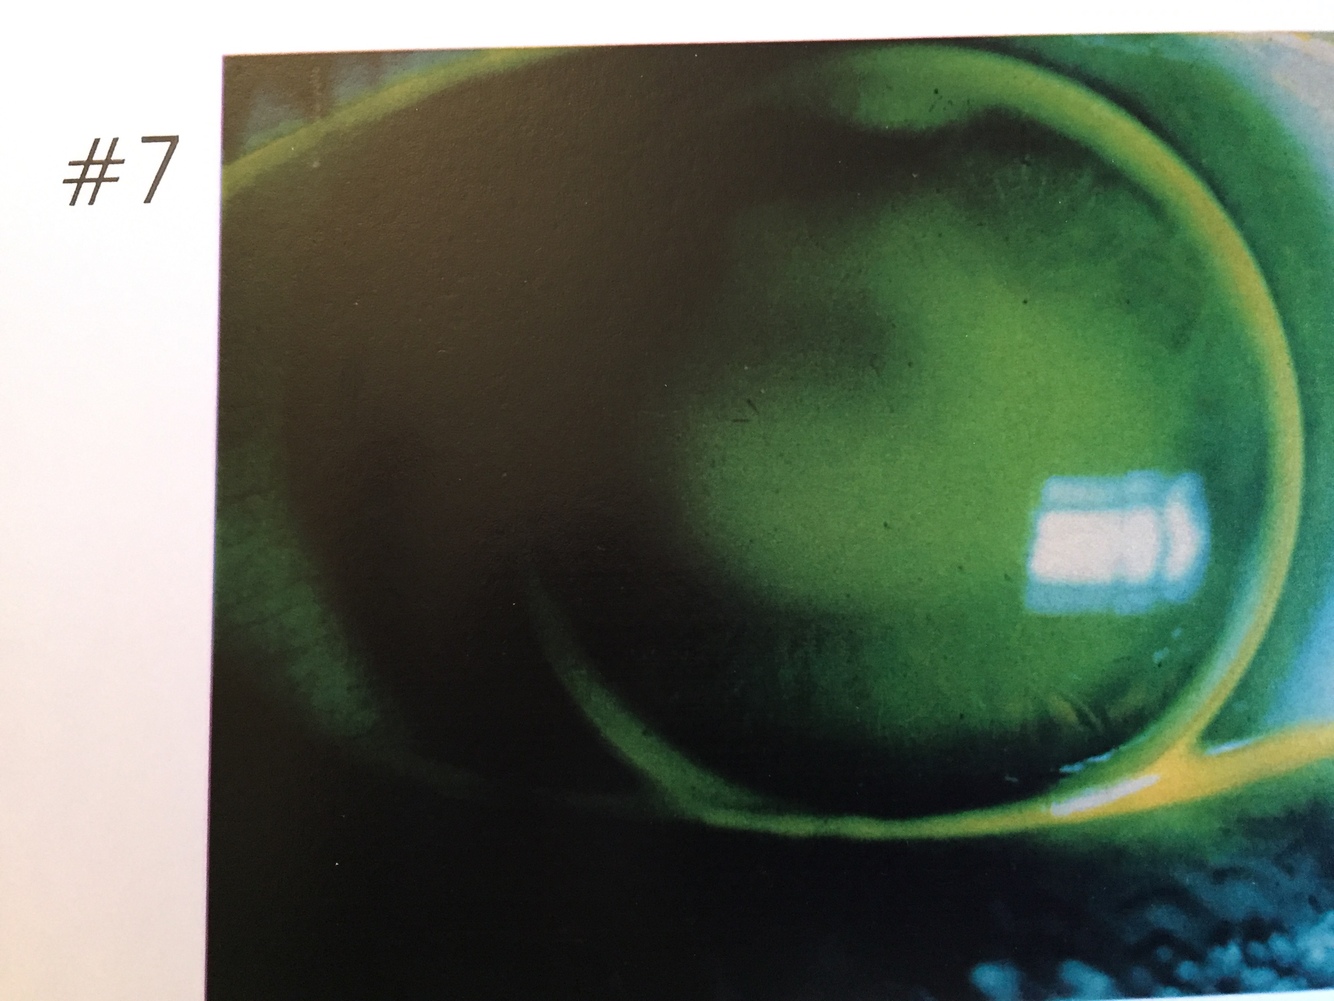

7.

Three Point Touch